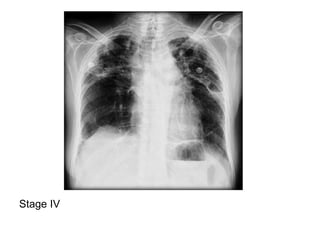

2-Classification :

-May be classified on a chest radiograph into 5

stages :

Stage 0 : normal chest radiograph

Stage I : hilar or mediastinal nodal enlargement

only

Stage II : nodal enlargement and parenchymal

disease

Stage III : parenchymal disease only

Stage IV : end-stage lung (pulmonary fibrosis)

Stage I

Stage II

Stage III

Stage IV